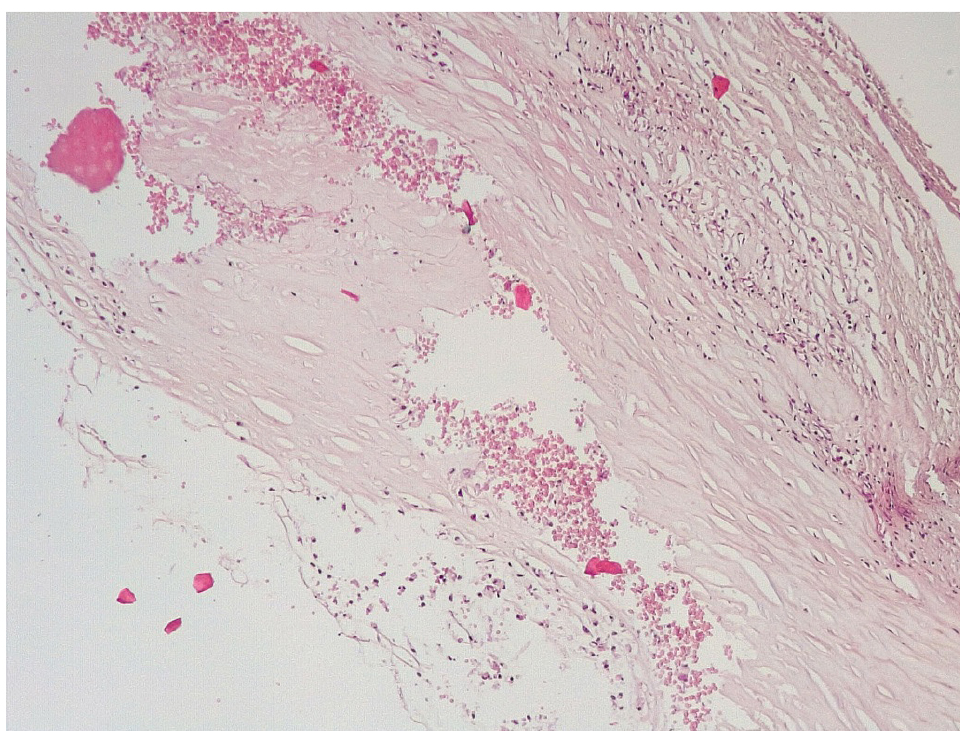

Позднее, спустя 3–7 суток после стентирования КА в просветах имелись пристеночные смешанные фибриново-лейкоцитарные тромбы, которые могли служить источником развития тромбоэмболических осложнений мелких дистальных ветвей коронарного кровотока и развитием острого инфаркта миокарда (рис. 4).

Рис. 4. Пристеночный смешанный (фибриново-лейкоцитарный) тромб в просвете КА (3–7-е сутки). Окраска гематоксилином-эозином. Ув. ×200